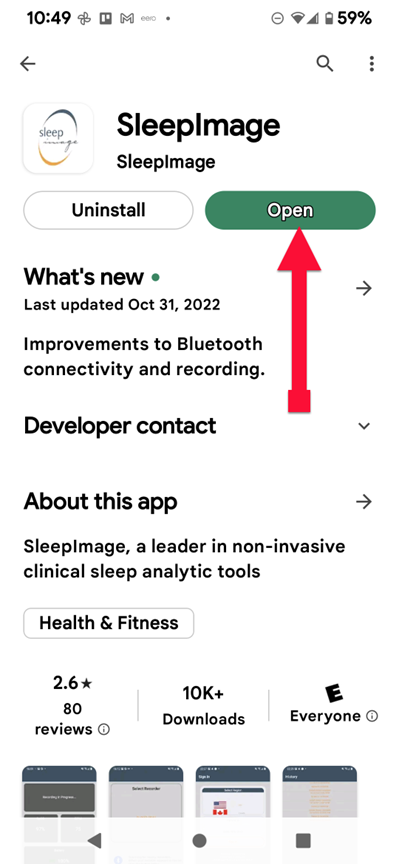

SLEEPIMAGE APP (Android)

SLEEPIMAGE APP (Android)

SLEEPIMAGE APP (Android)

SLEEPIMAGE APP (Android)

SLEEPIMAGE APP (Android)

SLEEPIMAGE APP (Android)

SLEEPIMAGE APP (Android)

SLEEPIMAGE APP (Android)

SLEEPIMAGE APP (Android)

SLEEPIMAGE APP (Android)

SLEEPIMAGE APP (Android)

SLEEPIMAGE APP (Android)

SLEEPIMAGE APP (Android)

SLEEPIMAGE APP (Android)

SLEEPIMAGE APP (Android)

SLEEPIMAGE APP (Android)

SLEEPIMAGE APP (Android)

SLEEPIMAGE APP (Android)

SLEEPIMAGE APP (Android)

SLEEPIMAGE APP (Android)

SLEEPIMAGE APP (iPhone)

SLEEPIMAGE APP (Android)

SLEEPIMAGE APP (Android)

SLEEPIMAGE APP (Android)

SLEEPIMAGE APP (Android)

SLEEPIMAGE APP (Android)

SLEEPIMAGE APP (Android)

SLEEPIMAGE APP (Android)

SLEEPIMAGE APP (Android)